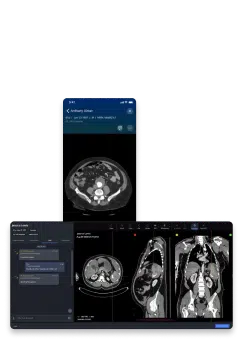

Viz Vascular is a comprehensive suite of AI-powered workflow solutions designed to enhance the efficiency and effectiveness of patient care for vascular teams. The platform optimizes clinical workflows by providing hyperfast vascular imaging across any device, reliable AI-powered screening for multiple vascular diseases, and real-time collaboration tools for efficient communication among care teams. It helps establish urgency and coordinate care by delivering relevant patient information promptly.

The suite includes specialized modules such as Viz™ Pulmonary Embolism, which offers AI-powered clot detection and automated RV/LV ratio calculation. This module securely detects and triages central and segmental embolisms, expediting treatment decisions and facilitating communication through a built-in chat. Another key module, Viz Aortic Disease, provides AI-powered detection of suspected abdominal aortic aneurysm (AAA) and aortic dissection. Viz.ai emphasizes unparalleled accuracy and performance, with published post-market validation demonstrating high sensitivity and specificity for PE, Aortic, and AAA detection. By improving diagnostic acumen and expediting critical decision-making, Viz Vascular aims to save lives and improve patient outcomes.

- Real-time Care Coordination: Facilitates efficient communication and collaboration among care teams with built-in chat and relevant patient information sharing.